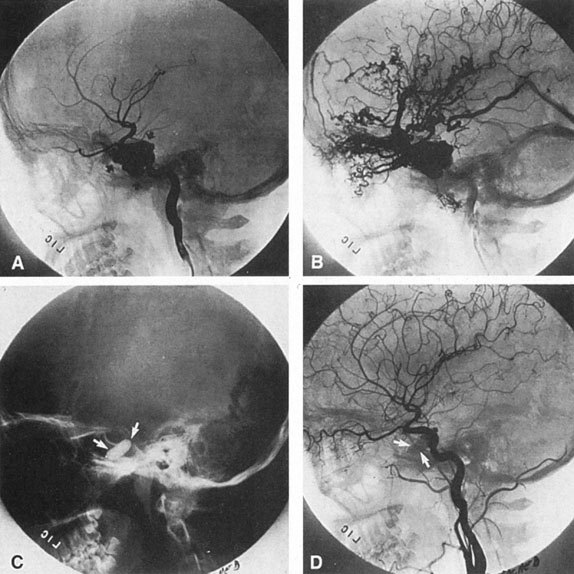

SUPRATENTORIAL

From 85% to 90% of AVMs are in the supratentorial compartment and are supplied primarily by the carotid circulation (Figs. 7 and 8). The remainder are supplied by the vertebrobasilar system. The approximate frequency of location is as follows: frontal, 22%; temporal, 18%; parietal, 27%; occipital, 5%; and deep intraventricular or paraventricular, 18%. The intracerebral site of the malformation does not necessarily indicate that there will be signs referable to that area simply from the mass effect of the malformation. Clinical features primarily result from subarachnoid hemorrhage or intraparenchymal hemorrhage with hematoma formation.

Fig. 7. Supratentorial arteriovenous malformation in a 28-year-old woman with a history of focal motor seizures for many years and a recent subarachnoid hemorrhage. A: Lateral projection carotid arteriogram demonstrating a huge deep hemispheral arteriovenous malformation. B: Frontal projection. C: Fundus photograph showing anomalous tortuous vasculature in each eye. No retinal arteriovenous shunt was detectable.

Fig. 8. Multiple supratentorial arteriovenous malformations (AVMs). A: Lateral projection of left carotid arteriogram shows dilated afferent artery (solid arrow) feeding the right hemispheric parietal AVM (open arrow). B: Right carotid injection fills a second, more posteriorly located, parietooccipital AVM (open arrow), which drains immediately to markedly dilated cortical veins (curved arrow).

In general, when hemorrhage occurs involving a portion of the visual radiations, a homonymous visual field defect is to be expected. Selective involvement of the anterior visual pathways may occur either with extensive venous angiomas at the base of the brain or as part of the Wyburn-Mason syndrome (see later), with direct involvement of the optic nerve, chiasm, or tract. Other variants such as congenital cavernous hemangiomas may involve the anterior visual pathways,68 as may intraparenchymal cryptic AVMs69 and present as symptomatic visual loss also resulting from hemorrhage and hematoma. Amaurosis fugax may even be the presenting symptom of supratentorial AVMs when blood is shunted to the meningeal circulation from the ophthalmic artery.70 When supratentorial AVMs drain into dural venous sinuses or the vein of Galen, distant ocular effects evolve, such as proptosis71 or ophthalmoplegia72 because of arterialization of cavernous sinus complex.

Of particular interest are those AVMs that involve the occipital lobe (Fig. 9). The clinical differentiation of migraine from a cerebral AVM was previously regarded as difficult because the clinical features of occipital lobe AVMs include visual phenomena or headaches. However, in most cases the clinical distinction is possible. In 26 cases with occipital AVM, two distinct syndromes were defined in 18 patients: occipital epilepsy and occipital apoplexy.73 Focal seizures with occipital malformations consist of elementary visual sensations similar to the phenomena evoked by direct cortical stimulations. When seizure activity occurs in the striate cortex (area 17), the patient usually reports sensations of moving lights in the right or left homonymous fields. The sensations are poorly formed, episodic, usually brief, sometimes colored, and unassociated with the angular, scintillating figures so characteristic of migrainous cortical phenomena. Epileptic discharges from areas 18 and 19 cause photopsias that are unlikely to remain stationary and to flicker rapidly. The epileptic photopsias usually last only seconds; occasionally they last for a few minutes before the onset of a generalized seizure. In other instances only the brief visual episodes occur without spreading to produce a generalized seizure. Momentary dimming or blindness in one or both homonymous fields may be experienced with seizure activity in the occipital areas.

Fig. 9. Carotid arteriogram of an occipital lobe arteriovenous malformation (AVM). Lateral (A) and frontal (B) projections demonstrating a small occipital AVM (arrow). The patient was a 23-year-old woman who presented with severe apoplectic unilateral headache, total left homonymous hemianopia, and mild nuchal rigidity. Despite xanthochromic cerebrospinal fluid, she was initially diagnosed elsewhere as having migraine. An AVM was successfully resected, and a small occipital lobe hematoma was removed.